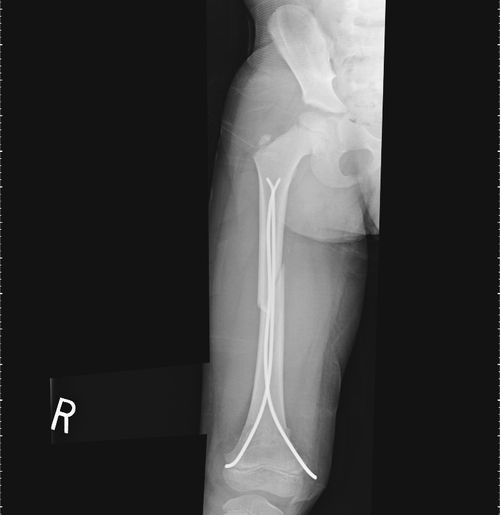

He was treated by flexible retrograde intramedullary rods with closed insertion under image guidance with good pos-top results.

His rods will be removed at three months and he is expected to make a full recovery.